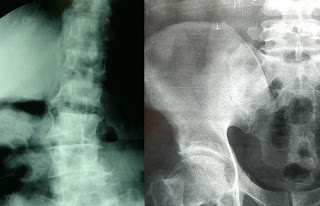

La osteoporosis, dijo el especialista, se produce en las estructuras óseas, principalmente las de tejido esponjoso, que se encuentran en la periferia o en los extremos finales de los huesos. Con el paso del tiempo éstas se gastan más rápidamente y disminuyen en grosor y cantidad, perdiendo su conectividad y su capacidad de soportar las cargas a las que originalmente se sometían.

Aclaró que como consecuencia, los huesos de caderas, codos, muñeca, rodillas y tobillos que se rompen son cada día más frecuentes. La osteoporosis no son las fracturas, pero éstas si constituyen la complicación real y grave del padecimiento.

De acuerdo con cifras de la Fundación Internacional de Osteoporosis, actualmente la fractura más común derivada de este padecimiento es la de los cuerpos vertebrales, pero la más costosa y con mayores complicaciones es la de cadera. Suele ocurrir con mayor frecuencia entre los 70 y 75 años.